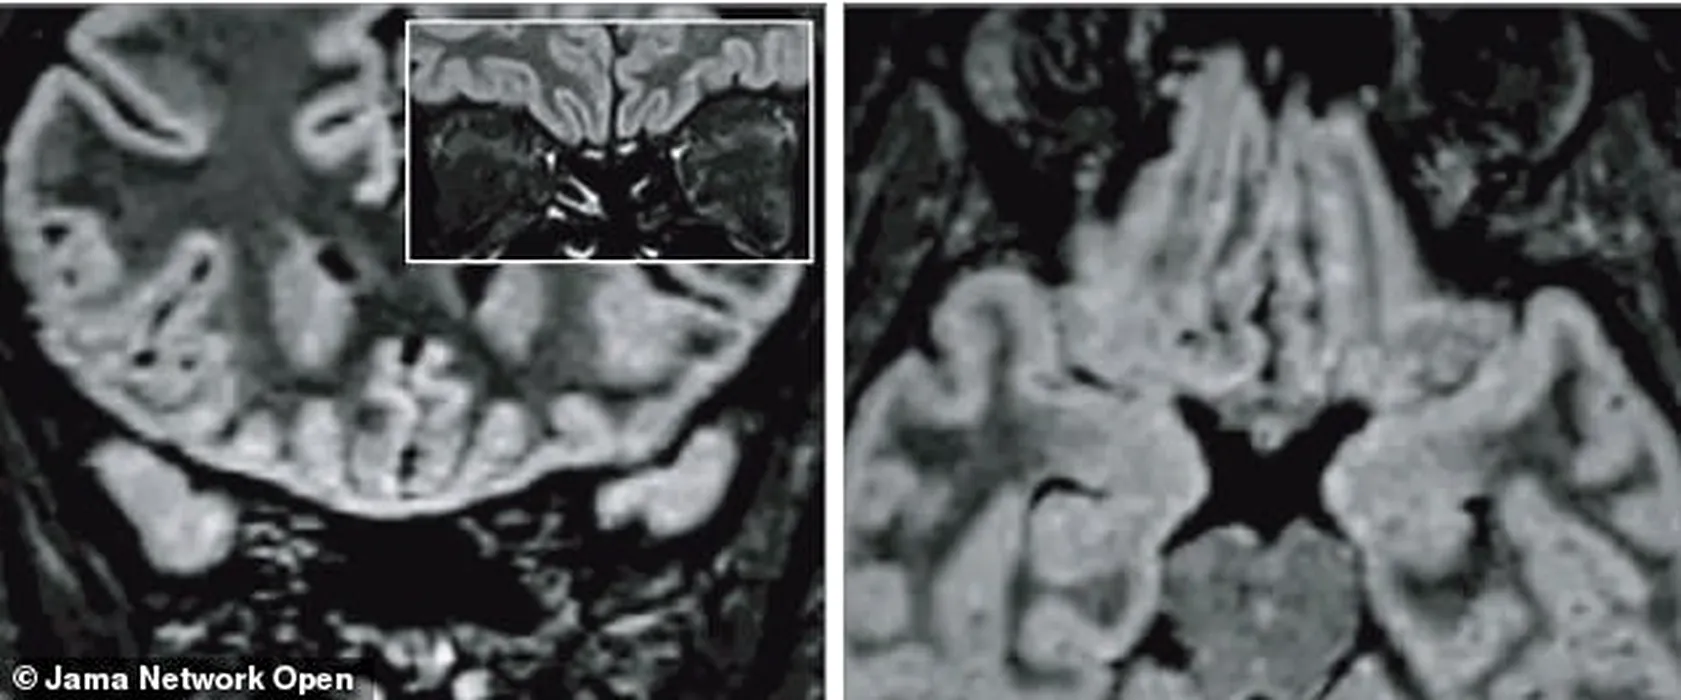

EFECTE. Cum s-a schimbat creierul unei tinere de 25 de ani care și-a pierdut simțul mirosului din cauza noului coronavirus

Cum s-a schimbat creierul unei tinere de 25 de ani care și-a pierdut simțul mirosului din cauza noului coronavirus